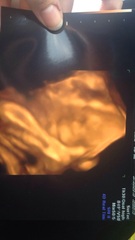

Wow Indians, so beautiful. The 4D scans are amazing.

My gorgeous boy yesterdaySmile giving us a thumbs up letting us know hes okay haha

puzzle & Indians - I love the 4D scans. You have inspired me and I am going to book one in shortly. I was thinking in about 3 weeks when I am around 32/33 weeks.

puzzle and indians great scan pics I'm so impatient to find out what my little girl will look like I think I might cave in and get one Smile

Indians and Puzzle love your scan pics. Where did you go? Does anyone know of anywhere good in the Yorkshire region to get them done?

Indians- the experience was lovely! The ladies were wonderful and so nice tried to get the best pictures possible but was hard because of how he was laying.. But I was told he's head down!!Grin I was to busy being an emotional wreck to ask questions such as thoughts on weight haha, but I do recommend going I loved it

Bel- I went to Window To The Womb in Southampton, they have a few studios around the UK so you could see if one is near you :)

I went at 17 weeks and 30+4 the other day, so I got to see how he's progressed!! Its amazing! (Pic attached)

Puzzle pics are amazing, sounds like you had a successful shopping trip!

Indians great pics, very clear.